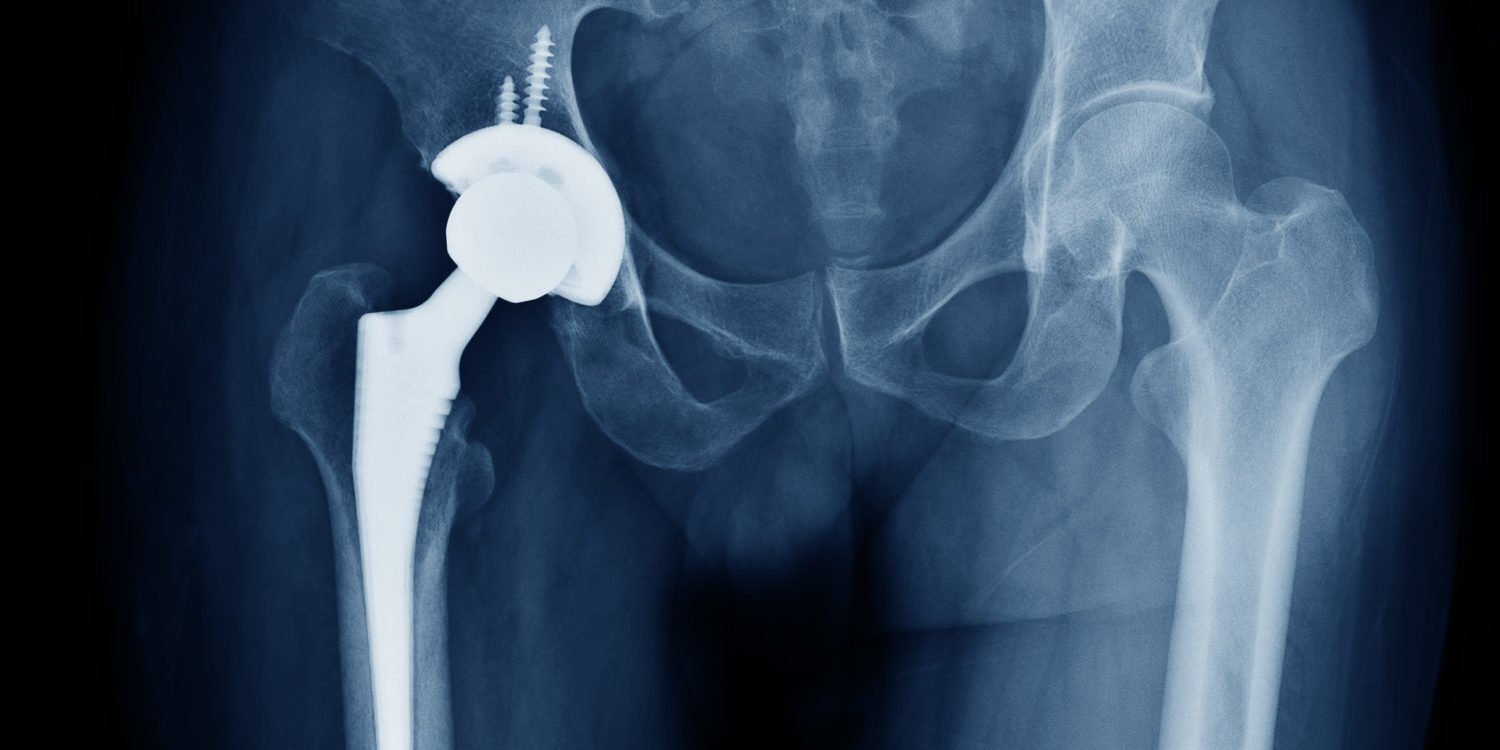

نحوه انجام جراحی تعویض مفصل لگن

تعویض مفصل لگن توسط پزشک جراح ارتوپد انجام میشود و در آن پزشک مفصل آسیبدیده بیمار را برمیدارد و یک مفصل مصنوعی را جایگزین آن میکند. این جراحی ۱ الی ۲ ساعت طول میکشد و میزان پیچیدگی عمل در بیماران مختلف متفاوت است.

قبل از شروع عمل جراحی، پزشک بیهوشی، بیمار را بیهوش میکند و بیمار تا پایان جراحی هیچ دردی را احساس نخواهد کرد. سپس در طی عمل جراحی، پزشک ارتوپد قسمتی از استخوان ران که در ناحیهی لگن دچار آسیب شده، از بدن بیمار خارج میکند و درنهایت تعویض مفصل لگن انجام میشود.